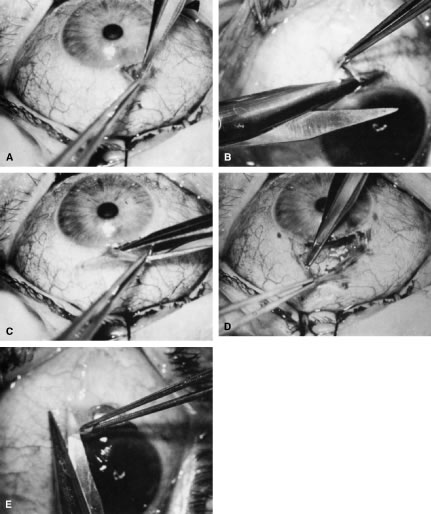

of a limbus-based flap appears unjustifiably difficult and risky.    Fig. 13. Limbus-based flap procedure. A. Conjunctiva is lifted away from the globe, stretched, and incised adjacent

to the superior rectus muscle bridle suture. B. The incision in the conjunctiva is extended nasally. C. The conjunctival incision is extended temporally. D. Tenon's capsule is lifted up, away from the globe, and incised with

the scissors held obliquely to avoid cutting into the underlying superior

rectus muscle. E. The incision in Tenon's capsule is spread bluntly. F. The superior rectus muscle can be seen through the buttonhole in Tenon's

capsule. Bleeding should be minimal; if it occurs, it should be

controlled promptly with cautery. G. Tenon's capsule is incised nasally and temporally. H. The connective tissue overlying the superior rectus muscle is seen easily

after Tenon's capsule has been incised. This tissue usually is

highly vascular in the area directly at the base of the superior rectus

muscle. I. Episclera is buttonholed approximately 4 mm posterior to the limbus, showing

the underlying sclera. J. One blade of the scissors is insinuated between the sclera and the episclera, and

the episclera is incised nasally. K. The episclera is incised temporally. The plane of the scissors is flush

with the sclera. L. Remaining adhesions between the episclera and sclera are dissected in

a semisharp fashion with the no. 67 Beaver blade, which is pushed at right

angles to the cutting axis. M. Tenon's capsule is closed in a separate layer with an 8-0 absorbable

suture. N. The superior edge of Tenon's capsule tends to retract up under the

lid. It can be hooked over the needle and pulled inferiorly. Sutures

are locked. O. After Tenon's capsule is closed, the needle is placed from the underneath

side to the superficial side of the conjunctiva and exteriorized

so that it can be used to close the conjunctiva. P. The conjunctiva is closed with closely spaced running, unlocked sutures. The

final suture is tied securely. Q. After the needle has passed through the tissue, it is lifted away from

the globe firmly. The underlying tissue is stretched. A blunt forceps

is used to grasp this underlying tissue firmly, as close to the needle

as possible. This maneuver will hold the needle firmly in place, permitting

the surgeon to release the end of the needle containing the suture

without having to change the position of the needle. R. The needle can be regrasped toward the cutting end so that it is held

in proper position for placement of the next suture. (Spaeth GL. Glaucoma surgery. In Spaeth GL (ed). Ophthalmic Surgery: Principles

and Practice. Philadelphia: WB Saunders, 1990.) Fig. 13. Limbus-based flap procedure. A. Conjunctiva is lifted away from the globe, stretched, and incised adjacent

to the superior rectus muscle bridle suture. B. The incision in the conjunctiva is extended nasally. C. The conjunctival incision is extended temporally. D. Tenon's capsule is lifted up, away from the globe, and incised with

the scissors held obliquely to avoid cutting into the underlying superior

rectus muscle. E. The incision in Tenon's capsule is spread bluntly. F. The superior rectus muscle can be seen through the buttonhole in Tenon's

capsule. Bleeding should be minimal; if it occurs, it should be

controlled promptly with cautery. G. Tenon's capsule is incised nasally and temporally. H. The connective tissue overlying the superior rectus muscle is seen easily

after Tenon's capsule has been incised. This tissue usually is

highly vascular in the area directly at the base of the superior rectus

muscle. I. Episclera is buttonholed approximately 4 mm posterior to the limbus, showing

the underlying sclera. J. One blade of the scissors is insinuated between the sclera and the episclera, and

the episclera is incised nasally. K. The episclera is incised temporally. The plane of the scissors is flush

with the sclera. L. Remaining adhesions between the episclera and sclera are dissected in

a semisharp fashion with the no. 67 Beaver blade, which is pushed at right

angles to the cutting axis. M. Tenon's capsule is closed in a separate layer with an 8-0 absorbable

suture. N. The superior edge of Tenon's capsule tends to retract up under the

lid. It can be hooked over the needle and pulled inferiorly. Sutures

are locked. O. After Tenon's capsule is closed, the needle is placed from the underneath

side to the superficial side of the conjunctiva and exteriorized

so that it can be used to close the conjunctiva. P. The conjunctiva is closed with closely spaced running, unlocked sutures. The

final suture is tied securely. Q. After the needle has passed through the tissue, it is lifted away from

the globe firmly. The underlying tissue is stretched. A blunt forceps

is used to grasp this underlying tissue firmly, as close to the needle

as possible. This maneuver will hold the needle firmly in place, permitting

the surgeon to release the end of the needle containing the suture

without having to change the position of the needle. R. The needle can be regrasped toward the cutting end so that it is held

in proper position for placement of the next suture. (Spaeth GL. Glaucoma surgery. In Spaeth GL (ed). Ophthalmic Surgery: Principles

and Practice. Philadelphia: WB Saunders, 1990.)